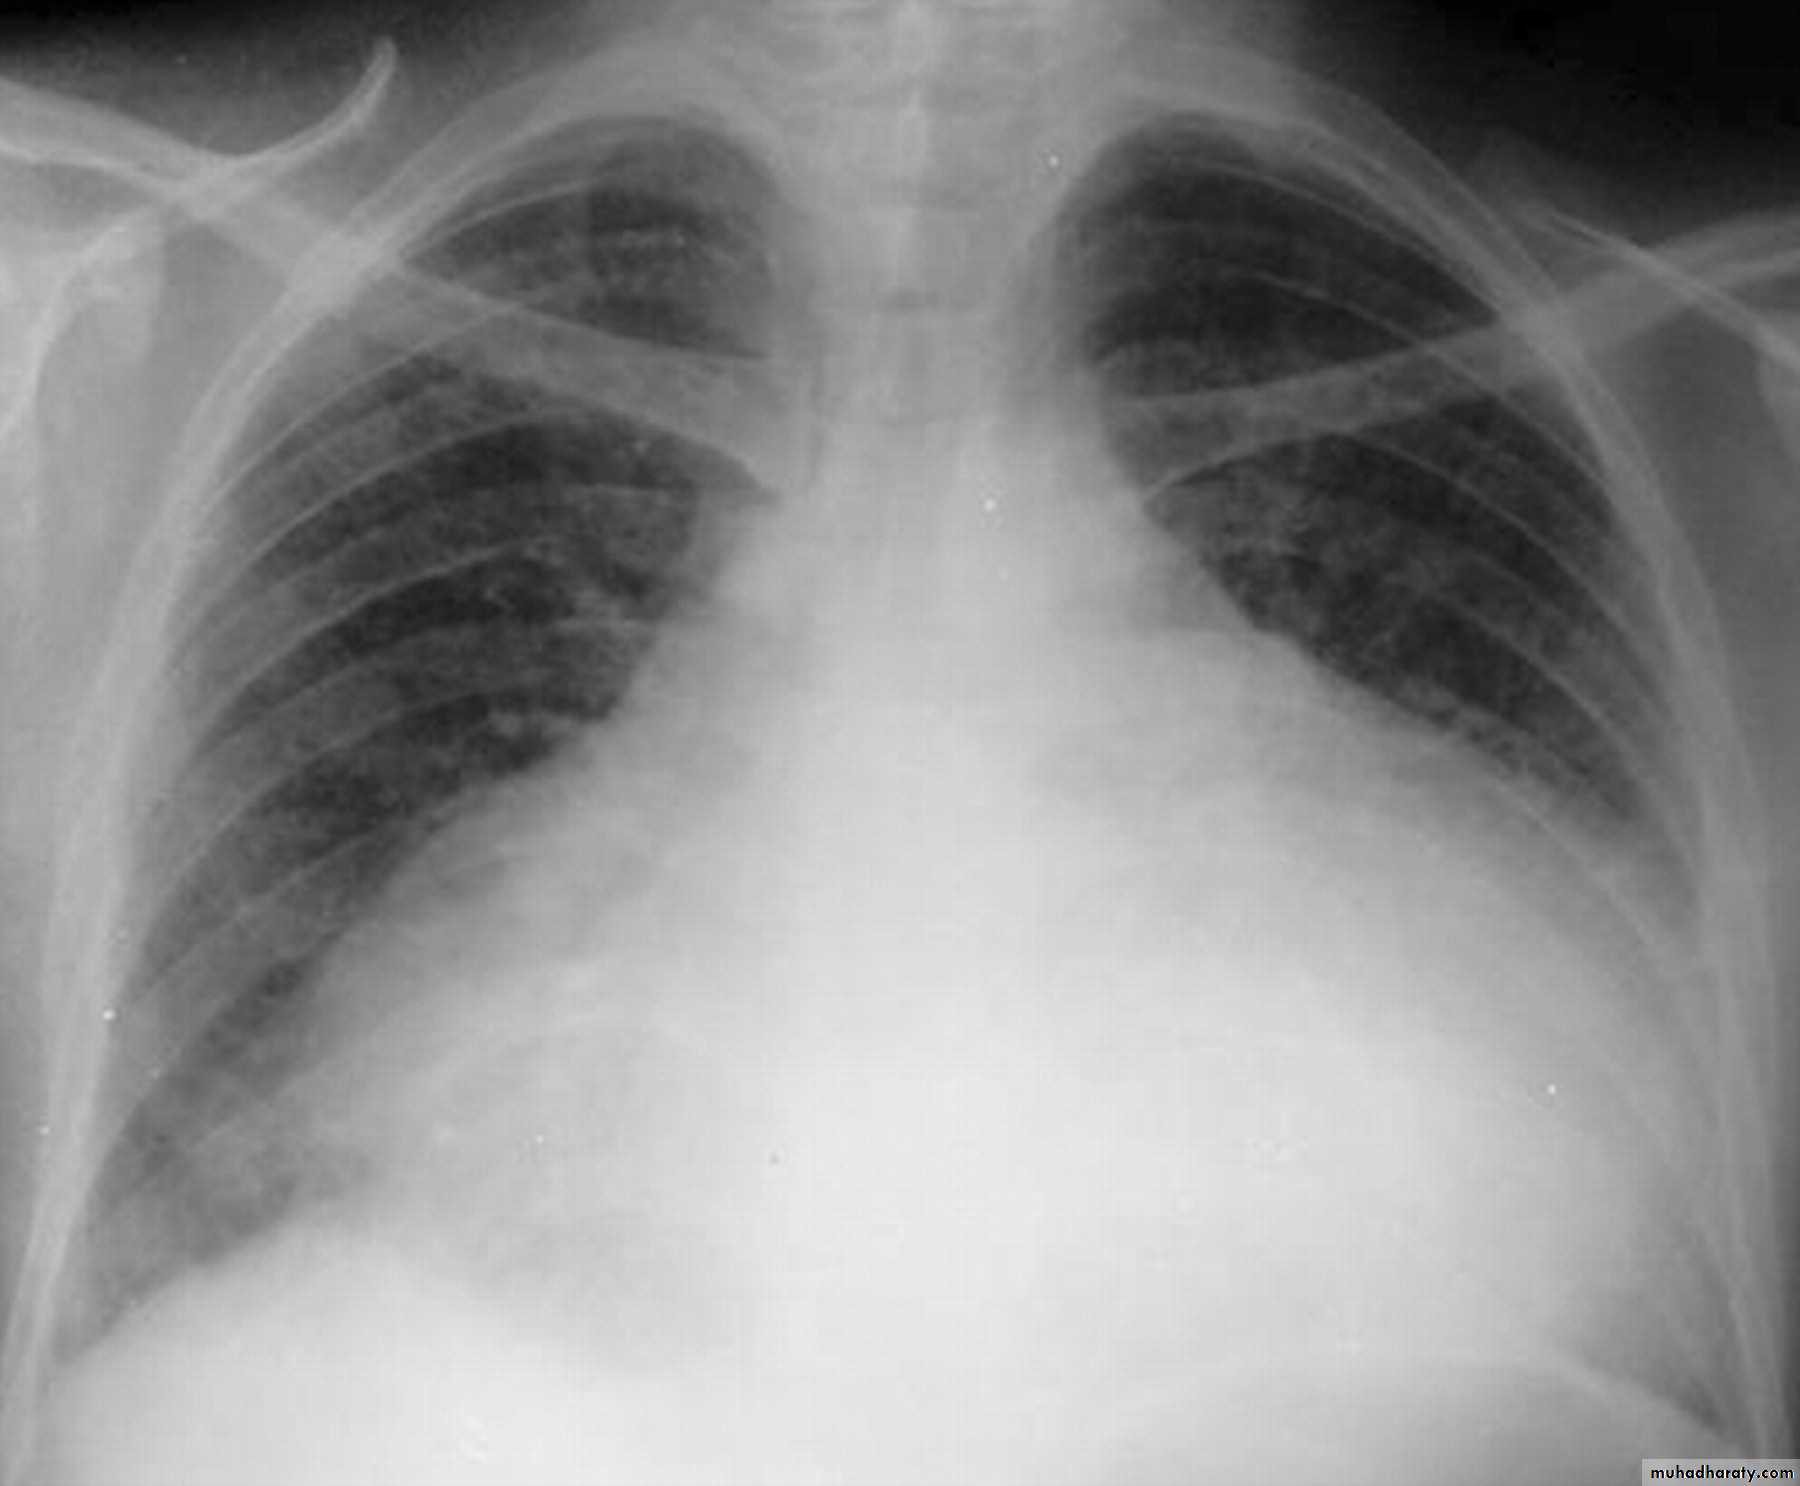

Pleural effusion

50.pleural effusion

51.pleural effusion .